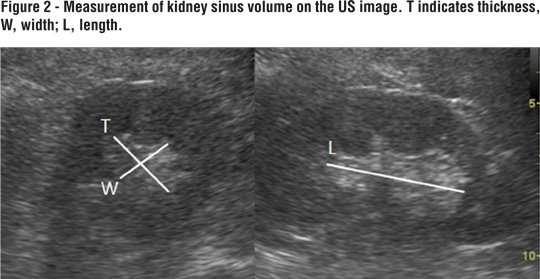

A systematic abdominal sonographic examination (4.5-5 MHz convex array transducer, Aloka alfa 6, Japan) was performed on all patients. The examination was performed with the subject in a supine and prone positions. Kidney measurements were obtained with the subject prone. Kidney length, width and thickness were measured using US. Kidney volume (total volume (Figure-1) and sinus volume (Figure-2)): lenght x thickness x width x 0.523 (5) were obtained. Parenchymal volume was calculated as total volume- sinus volume. RI was calculated automatically by Doppler US (Figure-3).